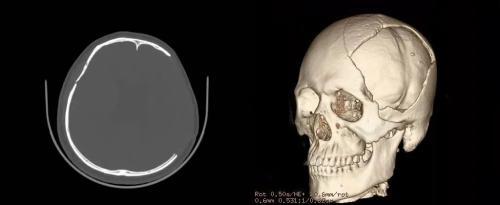

顱骨修補術前

顱骨修補術后復查